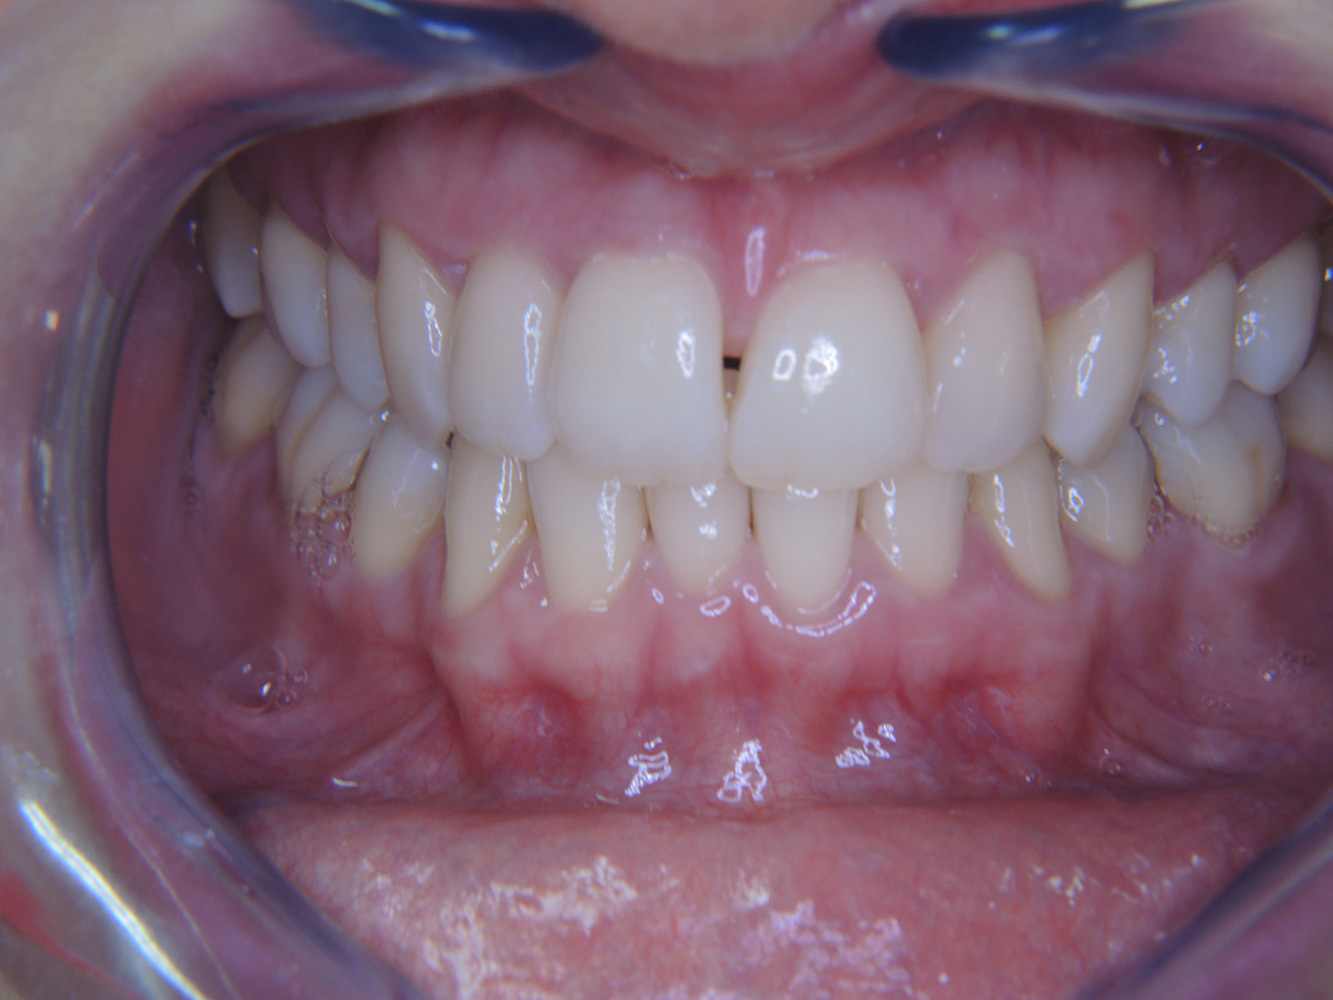

Următoarele studii de caz* acestea au rolul să ilustreze interacțiunea dintre necesitățile și factorii de risc definiți pentru IPC, precum și efectele factorilor individuali.

The (orally) healthy patient with implants

In the medical history, the 55-year-old patient states that he has no systemic disease and is not taking any medication. The patient’s lifestyle is similarly unremarkable. The patient has a few tooth restorations and two implants (2nd and 4th quadrants). On the basis of current findings, gingivitis is identified in an otherwise stable periodontal condition on the reduced periodontium (stage III, grade A). more